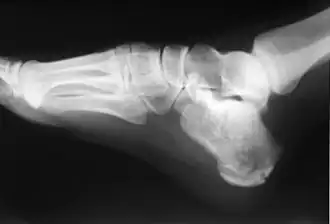

Le calcanéus (ou calcanéum en ancienne nomenclature) est le plus volumineux des os du tarse (talon). Il constitue la partie postéro-inférieure de celui-ci et le pilier postérieur de l'arc longitudinal du pied. Il est situé sous le talus.

Le calcanéus a la forme parallélépipèdique, plus haut que large, à grand axe allongé en avant, en haut et en dehors.

Il présente six faces.